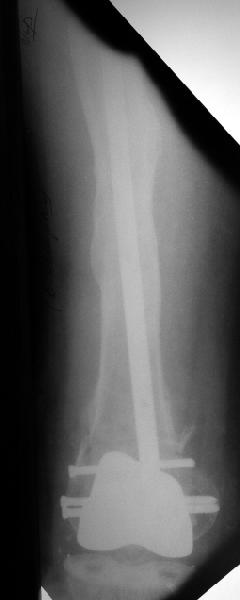

Глубокоуважаемые коллеги, Мужчина 41 года поступил с повторным (предыдущий в 2001 г.) переломом (3-недельной давности) над протезом коленного сустава.

В 1994 множественная травма, в том числе открытый перелом надколенника, осложнившийся гнойным артритом, и на этой же стороне перелом диафиза бедра (лечили в аппарате). В 1998 г. выполнено эндопротезирование коленного сустава.Предыдущий перелом (3 года назад) лечили консервативно, сросся при неустраненном смещении дистального блока бедра кзади ~ на 1 см.Амплитуда движений в коленном суставе перед последним переломом была ~90 градусов. Ходил без дополнительной опоры.Снимки в приложении. Какие будут предложения по поводу оперативного лечения в нынешней ситуации? У нас споры между ретро- и антеградным закрытым интрамедуллярным остеосинтезом.

A male 41 years old transferred to our unit with 3 week old femoral fracture near the knee prosthesis after a mimimal fall. In 1994 he sustained multiple injury with open patella fracture (complicated with septic arthritis), and ipsilateral femoral shaft fracture treated by ex-fix. TKA performed in 1998. In 2001 he got a periprosthetic fracture which was treated nonoperatively and healed with ~1 cm dorsal displacement of the distal femoral block. Knee ROM prior the recent injury was about 90-95 degrees. He didn't use walking aid.Images attached. I request your suggestions regarding surgical options in the situation? We mostly discuss ante- vs retrograde closed nailing.